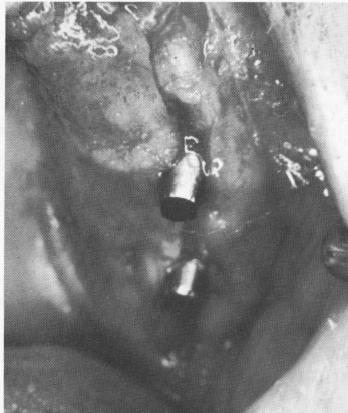

Fig. 7-41. The overlying tissues are too thick, burying the abutment posts of the blade.

1 Thick tissues overly endosseous blade implant abutment posts